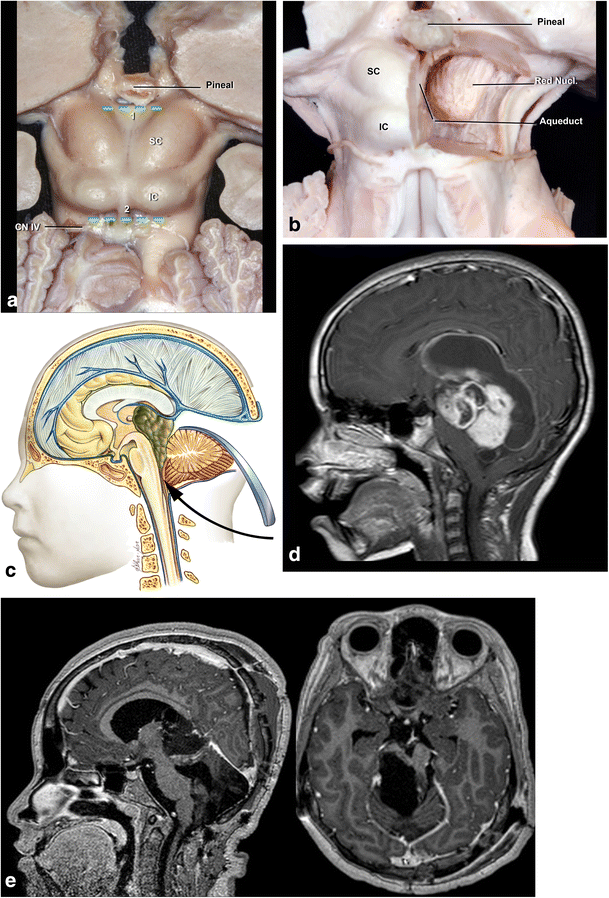

Fig. 6

figure 6

a. Tumors located at the central portion of the midbrain and growing towards the pineal region. b Infratentorial supracerebellar approach. c Anatomical view of pineal region via the infratentorial supracerebellar route. SC superior colliculus, IC inferior colliculus

Fig. 7

figure 7

a, b A solid cystic tumor at the central portion of the midbrain with gadolinium enhancement growing towards the pineal region was removed by a central infratentorial supracerebellar approach. c, d 10-year follow-up shows no evidence of the lesion, which was a pilocytic astrocytoma